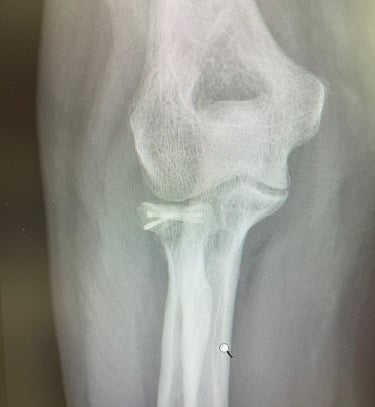

Mi occupo del trattamento traumatico sia in forma conservativa sia chirurgica. Tratto fratture, lussazioni, lesioni dei legamenti e dei tendini, con l’obiettivo di ripristinare la funzionalità articolare, ridurre il dolore e favorire un rapido ritorno alle attività quotidiane e sportive.